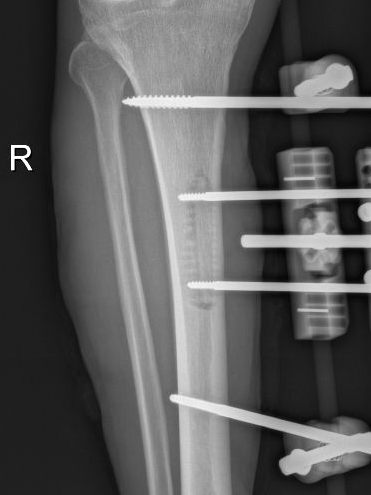

12月17日,贵州航天医院第88次晨读会由我院骨一科主任、副主任医师陈明勇作学术交流,他以“肱骨近端骨折并肩关节脱位的手术治疗”为题,全面讲解了该损伤的手术策略、术中血供保护理念及内侧支撑重建技术等内容,并通过多个典型病例图文资料分享了从损伤机制分析、手术步骤实施到术后随访评估的完整过程与关键细节,为临床处理此类复杂骨折提供了较为全面的技术参考,有助于在手术规划中结合个体情况开展针对性治疗。 贵州航天医院 骨科专家简介 陈明勇 骨一科主任,副主任医师 临床擅长:从事创伤骨科工作约20年,对骨缺损、骨不连、骨肿瘤、肢体畸形等的肢体矫形重建及功能重建,慢性化脓性骨髓炎的根治治疗、糖尿病足的保肢治疗、快速康复理念(ERAS)下的老年骨折的诊治,四肢复杂骨折的诊治,四肢骨折等微创手术治疗具有丰富的临床经验。 2004年毕业于遵义医学院临床专业,曾在中国人民解放军总医院、广西医科大学第一附属医院、上海第六人民医院骨科进修。中国中西医结合学会骨伤科专业委员会横向骨搬移治疗糖尿病足及微血管网再生学组首届委员,遵义市医学会创伤分会常务委员。 瞿 晖 骨科党支部书记,骨二科主任,副主任医师 临床擅长:对骨科的常见病、关节外科、脊柱外科及运动医学疾病的诊治具有丰富的临床经验,熟练掌握骨科手术操作技术。 毕业于遵义医学院临床医学系,2005年前往广州中山大学第一附院骨显微医学部进修学习,2011年前往成都华西医院进修学习,并多次在省内外学习骨科相关知识,是中华医学会骨科分会会员。 赵小锋 中共党员,骨二科副主任,副主任医师 临床擅长:从事骨科临床工作11年,对骨科常见病、多发病诊疗有较为丰富的临床经验,擅长脊柱相关疾病诊断及治疗,尤其是颈、腰、腿疼痛疾病诊断及治疗,擅长胸腰椎骨折微创经皮穿刺内固定术、经皮穿刺椎体成形术、经皮穿刺脊柱内镜下腰椎间盘摘除术、单纯开创腰椎间盘摘除术、腰椎滑脱复位椎间植骨椎融合内固定术、腰椎管狭窄减压融合内固定术及人工髋、膝关节置换术等。 2012年毕业于遵义医学院外科学专业硕士研究生,2019年参加“遵义市115医学人才精英计划”于上海交通大学第一附属医院培训学习,2023年于北京大学第三人民医院脊柱外科进修学习,曾获得遵义市优秀医师荣誉称号。 遵义市手外科第一届委员,遵义市医学会创伤分会第一届委员,遵义市医学会创伤分会第二届委员,贵州省康复医学会第三届脊柱脊髓专业会委员,遵义市医学会烧伤与整形外科学分会委员,发表论文5篇,其中国家级核心期刊1篇,SCI论文1篇,主持市级课题1项并结题,参与市级课题2项。 赵兴东 骨科主任医师 临床擅长:擅长骨科的常见病及各种创伤、四肢骨折创伤修复、骨感染、手足疾病的诊治和手足体表畸形的矫形整复,熟练掌握骨科四肢骨病及创伤的手术操作技术,尤其在四肢关节复杂性损伤、手足外伤、组织缺损创面、难治创面的皮瓣修复方面及平足、高弓足矫形方面及四肢慢性疼痛诊治、康复方面具有丰富的临床经验。 硕士研究生,毕业于遵义医学院临床外科系,2015年前往山东省立医院手足外科进修学习;遵义市医学分会创伤分会第一、二届委员,遵义市手外科医学会第二委届员会常务委员;在省级及省级以上期刊发表文章9篇,参编著作2部,参与主持并完成市级课题1项,参与市级课题2项、省级课题1项。 张艳金 中共党员,骨科副主任医师 临床擅长:从事骨外科工作16年,对复合伤、多发伤的救治、四肢骨干骨折、关节周围骨折、骨肿瘤、骨髓炎等诊治具有丰富的临床经验。 中共党员,硕士研究生,2006年本科毕业于山西医科大学第二临床医学院,2011年研究生毕业于北京军区总医院;在“老年COPD患者合并髋部骨折的诊治”国际合作课题组研究两年,在老年髋部骨折的诊治方面具有丰富的经验,并发表论文6篇;主持遵义市级课题1项,承担遵义医科大学的临床教学工作,获得遵义医科大学优秀带教老师荣誉。编撰有《骨科疾病诊疗精粹》一书,开展2项新技术,编撰地方规范《务川自治县创伤骨科常见疾病诊疗规范》一书。 张俊凯 骨科副主任医师 临床擅长:从事骨科临床工作28年,对创伤骨折、骨感染、骨缺损、骨不连等外科诊治,四肢骨折的微创手术治疗,四肢复杂骨折(如关节内粉碎性骨折、多发骨折等)的损伤控制及手术治疗等具有丰富的临床经验。 1995年毕业于遵义医学院临床专业,2009年前往复旦大学附属医院骨科进修1年。 卢懿明 中共党员,骨科副主任医师 临床擅长:从事骨科工作18年,对创伤骨折、四肢骨折的微创手术治疗、四肢复杂骨折(如关节内粉碎性骨折、多发骨折等)的损伤控制及手术治疗,尤其是髋部骨折的PFNA等微创技术,踝关节骨折、膝关节周围骨折的Mipo微创技术等具有丰富的临床经验,开展了4项新技术,发明6项新型专利技术。 2005年毕业于遵义医学院临床专业,2017年,前往南方医科大学第三附属医院骨科进修半年,回院后运用Mipo技术对骨干骨折及干骺端骨折的治疗技术,同时积极开展骨盆骨折、髋臼骨折腹直肌外侧切口的应用;发表了多篇专业论文,经常参与省内外学术交流会授课,获得医院荣誉称号多个。 邬夏荣 骨科副主任医师 临床擅长:从事骨科工作16年,对四肢复杂骨折、骨肿瘤的诊治,尤其是足踝创伤、慢性踝关节损伤、平足症等诊疗具有丰富的临床经验。 2006年毕业于遵义医科大学临床医学专业,曾在陆军军医大学西南医院进修学习,发表多篇骨科学术论文。 余德怀 中共党员,骨科副主任医师 临床擅长:从事骨科工作10余年,对运动医学、骨关节、脊柱外科常见病、多发病的诊治具有丰富的临床经验。 硕士研究生,2011年毕业于遵义医学院临床医学专业,曾前往遵义医科大学附属医院运动医学专业进修学习;是贵州省医学会运动医学分会青年委员,西部关节镜联盟委员;发表多篇骨科学术论文。 冯 乾 骨科副主任医师 临床擅长:从事骨科工作近20年,熟练掌握骨科多发病及常见病的诊治,尤其对脊柱退变性疾病的诊断及治疗具有丰富的临床经验,主要研究脊柱微创相关治疗方式,能熟练开展椎间孔镜及UBE。 曾前往北京大学第三医院进修学习疼痛及椎间孔镜、首都医科大学友谊医院专业进修脊柱内镜;是贵州省康复医学会第三届脊柱脊髓专业委员会委员;发明专利3项、发表脊柱外科专业论文多篇。 贵州航天医院骨科简介 基本情况 贵州航天医院(原3417医院)骨科组建于1968年,前身是以创伤和断肢(断指)再植闻名于世的上海市第六人民医院骨科,中国断肢(断指)再植的奠基者、中科院院士陈仲伟等专家莅临科室指导医疗和教学,并在70年代开展了贵州省首例断肢(断指)再植手术。组建50余年来,诊治患者已逾百万,挽救了无数的伤病员,成为了保障遵义地区人民群众健康的重要支撑。 经过几代人的不懈努力,今天的骨科,已由创伤骨科发展至骨病、骨肿瘤、骨结核等领域,现有脊柱外科、关节外科、四肢创伤、手足外科四个亚专科,成为了集医疗、教学、科研于一体的综合学科,是贵州省临床重点专科、遵义市临床重点专科、遵义市骨科临床医学中心、遵义市基层骨科专科联盟理事长单位。 科室目前开放床位110张,共有医护人员50余人,副高级以上专家18人,硕士研究生15人。拥有一流骨科医疗设备多台,每年不定期选派优秀技术骨干到全国各大知名医学院校进修、学习、参观、交流,并邀请国内、国外知名专家教授来院进行交流、指导,通过不断引进国内外先进的诊疗技术,科室医疗技术水平稳步提升,为广大人民群众提供了优质的医疗服务。 专科特色 骨一科 (一)骨缺损、骨不连的肢体与功能重建 胫骨横向骨搬移技术治疗糖尿病足: (二)慢性骨髓炎的根治治疗 (三)肢体缺血性疾病如糖尿病足、脉管炎的保肢治疗 (四)皮瓣修复 (五)复杂创伤的治疗 (六)老年髋部骨折及小儿骨折快速手术 老年髋部骨折: 骨二科 (一)胸腰椎骨折微创经皮椎弓根螺钉固定术 (二)老年性骨质疏松性患者腰椎滑脱脊柱内固定术(骨水泥螺钉) (三)V形双通道脊柱内镜技术(VBE)腰椎融合术治疗腰椎退行性疾病 (四)老年性骨质疏松性骨折(PVP/PKP)术 (五)人工髋关节置换术 (六)双侧股骨头坏死人工全髋关节置换 (七)右侧全髋置换术后假体周围骨折翻修 (八)人工膝关节置换术 (九)人工膝关节假体松动翻修 (十)关节镜技术 传统手术切口 关节镜技术切口 诊疗范围 骨一科 1.四肢创伤、矫形。 2.手、足踝外科。 骨二科 end